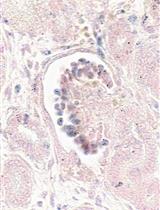

A recent study by Ouchi and colleagues described a protocol for the generation of a multicellular human liver organoid (HLO) composed of hepatocyte-like cells, hepatic stellate–like cells, and Kupffer-like cells from iPSCs [9]. The cells aggregated to form a 3D liver organoid that was used to model steatohepatitis after the addition of free fatty acids to the culture media [9]. In this paper, we describe a method for generating multicellular 3D liver organoids (Figure 1) adapted from the protocols published by Ouchi and colleagues [9] and Mun and colleagues [8]. We further describe in detail how to generate these organoids and demonstrate their utility as a tool to study downstream assays for liver disease models.